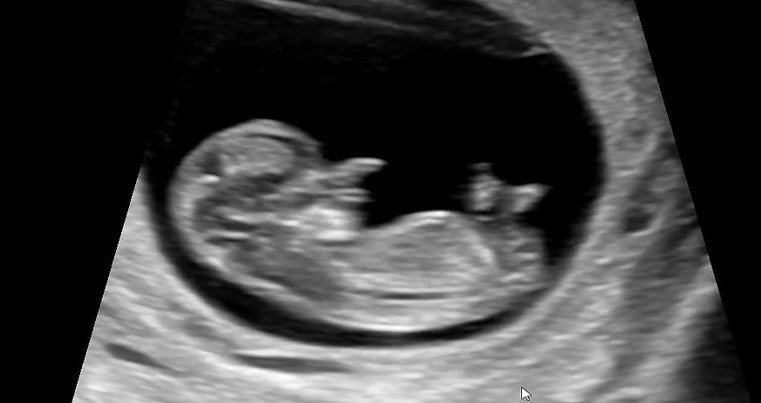

각도법봐주세용

아직 10주3일이지만 각도법으로 한번 봐주세옹~!🥹

아들이요!!!!

아들에한표요

이사진으론 안보이는거같아용